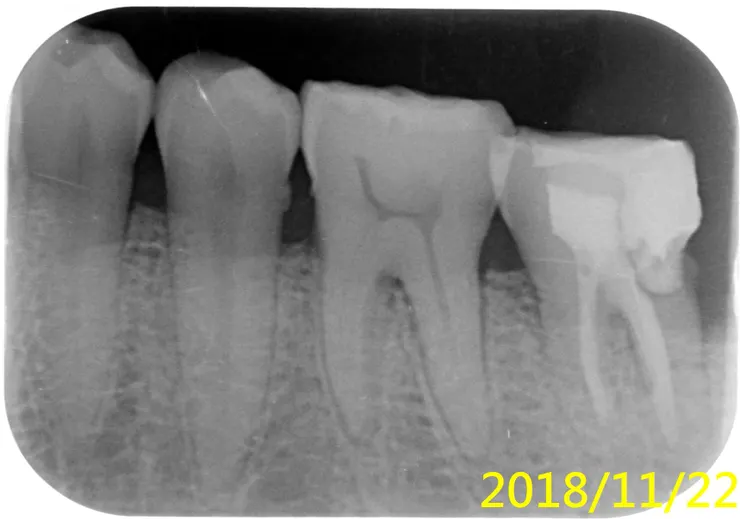

#38智齒拔完後,惡夢還沒結束,還要面對#37的根管治療(抽神經)

一年後,病人回來說,補的掉了

2018時我就已跟病人說的很清楚了,這裡就不贅言,直接引用張添皓醫師的文章說明『根管治療後,不做牙套,是多麼的危險,會導致前功盡棄(保留牙齒廢物利用,不要拔牙)』,何況他的情況,還不能直接做假牙,要先做『牙冠增長術』......所以,為了幫智齒擦屁股、收拾爛攤子,您看事後要付出多大的代價....